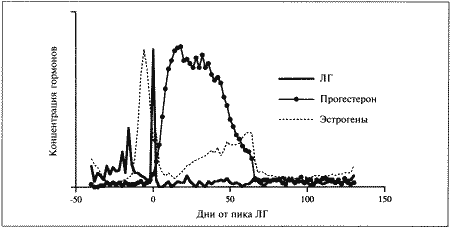

Фиг. 1.1.

Изменения концентрации эстрадиола (●), лютеинизирующего гормона (ЛГ,) и прогестерона (∆) в сыворотке крови у сук. На графике за точку отсчета принят день пика концентрации ЛГ. Следует отметить, что пик концентрации эстрадиола приходится на день минус 1, уже на день 0 заметно повышение концентрации прогестерона. (Перевод единиц: 1 пг/мл эстрадиола = 3,6 пмоль/л; 1 нг/мл прогестерона = 3 нмоль/л)

Стадия проэструса характеризуется развитием фолликулов под влиянием гонадотропных гормонов — лютеинизирующего (ЛГ) и фолликулостимулирующего (ФСГ), выделяемых передней долей гипофиза. Секреция этих гормонов регулируется гипоталамическим гонадотропинрилизинг гормоном (ГнРГ). У собак, так же, как и у других животных, вслед за пиком концентрации эстрадиола возникает (спустя сутки или чуть больше) пик концентрации ЛГ (фиг. 1.1). Таким образом, выброс ЛГ происходит всегда автоматически вслед за повышением активности фолликулов, вырабатывающих эстрадиол, и поскольку овуляция следует за возникающим без внешней стимуляции пиком концентрации ЛГ, ее называют спонтанной. Описанная ситуация разительно отличается от картины, которую можно наблюдать у кошек, для которых характерна индуцированная овуляция: у них выброс ЛГ и овуляция происходят вслед за коитусом. Насколько можно судить, у таких животных эстрадиол не способствует активации секреции ЛГ.

Повышение уровня ФСГ необходимо для стимуляции развития фолликулов и секреции эстрадиола, однако концентрация ФСГ в крови не достигает столь высоких значений, какие наблюдаются при пике ЛГ; это объясняют действием ингибина — белка, секретируемого фолликулами, который избирательно подавляет секрецию ФСГ Тем не менее ФСГ играет важную роль в созревании фолликулов и подготовке их к трансформации в желтые тела после овуляции. Начало трансформации фолликулярных клеток рассматривают как ключевой момент всего цикла, поскольку оно сопровождается преовуляторным повышением секреции прогестерона (фиг. 1.1), которое, по-видимому, играет ведущую роль в пусковом механизме овуляции и подтверждении эструса. Наблюдаемый у собак преовуляторный рост концентрации прогестерона нетипичен для других домашних животных, в частности для жвачных, у которых наступление эструса и овуляции происходит на фоне минимального уровня прогестерона. Однако преовуляторная концентрация прогестерона у собак все же относительно низка, и следует помнить, что назначение высоких доз прогестагенов в период проэструса вызывает отсрочку эструса и овуляции.

Овуляторный пик ЛГ обычно описывают как кульминацию цикла, что объясняется его ролью в процессах овуляции и перехода к метэструсу, т. е. к лютеиновой фазе, поддерживаемой прогестероном. По причинам, изложенным выше, а также потому, что момент наступления эструса у разных сук варьирует, для оптимального подсчета сроков беременности за точку отсчета принимают пик ЛГ, а не первый день эструса, как практикуется в работе с другими видами животных.

Овуляция

Повышение концентрации прогестерона является необходимым условием овуляции; соответственно начальное увеличение концентрации этого гормона в плазме происходит непосредственно перед овуляцией и может использоваться как индикатор ее приближения.

Как правило, у сук наблюдается множественная овуляция; согласно данным гистологических и лапароскопических исследований, в большинстве случаев овуляция происходит в течение 30–48 часов после пика концентрации ЛГ, хотя часть фолликулов овулируют лишь через 96 часов. После овуляции, но до оплодотворения ооциты проходят очередную стадию мейоза. Этот процесс с трудом поддается изучению, однако тщательный хронометраж искусственного осеменения замороженной спермой, взятой от разных кобелей (для упрощения идентификации потомства), приводит к выводу, что созревание ооцитов занимает 2–3 дня. Если сложить их с количеством дней, отделяющих пик концентрации ЛГ от овуляции, то получится, что оплодотворение возможно не раньше, чем через 4 дня, считая от пика концентрации ЛГ; этот день является началом фертильного периода (фиг. 1.2). Ошибки в его вычислении объясняются тем, что признаки эструса наблюдаются уже за 5 дней до начала фертильного периода и продолжаются еще 5 дней после его окончания. Следующие факторы определяют длительность фертильного периода: длительное (до нескольких дней) сохранение жизнеспособности спермы в половом тракте суки; время, необходимое для овуляции и созревания ооцитов (2–3 дня) при сохранении жизнеспособности яйцеклеток (1–2 дня). С учетом этих факторов фертильным следует признать период, продолжающийся от 4-го до 7-го дня, считая от пика концентрации ЛГ. При стандартном подсчете продолжительность беременности составляет от 58 до 72 дней, но если принять за точку отсчета овуляторный пик ЛГ, длительность беременности составит 65 дней с очень небольшими отклонениями.

Фиг. 1.2.

Динамика концентрации прогестерона в плазме крови на протяжении эстрального цикла. Составлено на основании данных, полученных при наблюдении за 8 собаками. За точку отсчета принят овуляторный пик ЛГ. Ключевые показатели, используемые для идентификации стадии цикла и вычисления фертильного периода (см. текст): концентрация прогестерона в конце анэструса находится на базальном уровне (может не выявляться) (х-х), затем в период проэструса незначительно повышается до определяемого уровня (о-о); в период, предшествующий овуляции, концентрация прогестерона возрастает одновременно с пиком ЛГ (+-+). За временной интервал между пиком ЛГ (▲-▲) и овуляцией уровень прогестерона повышается до характерных значений начала фертильного периода и продолжает увеличиваться (-•) приблизительно до 30 дня.

Эти хорошо известные функции двух главных стероидных гормонов, вырабатываемых яичниками, имеют равное значение для сук, несмотря на сравнительно более раннее изменение соотношения эстроген/прогестерон в результате преовуляторной лютеинизации (фиг. 1.1). На основании вышесказанного мы можем заключить, что в организме сук прогестерон обеспечивает выживание, транспорт и оплодотворение гамет, однако все это требует предварительного повышения концентрации эстрадиола (проэструс). У собак — как и у других видов — изменение соотношения эстроген/прогестерон в результате приема после овуляции фармакологических препаратов на основе эстрогенов увеличивает проходимость маточных труб, что приводит к слишком раннему попаданию эмбрионов в матку. На этом явлении основана посткоитальная эстрогеновая терапия.

Данные о концентрации прогестерона в сыворотке крови могут служить ориентиром для определения фертильного периода у сук. Механизмы и динамика изменения концентрации прогестерона описаны в предыдущем разделе (фиг. 1.2).

В конце анэструса концентрация прогестерона в сыворотке крови находится на базальном уровне (и практически не определяется), к окончанию проэструса она повышается до низкой, но поддающейся определению отметки (около 3 нмоль/л или 1 нг/мл). И продолжает повышаться, достигая уровня 3–6 нмоль/л (1–2 нг/мл) к моменту овуляторного пика ЛГ; 2 дня спустя (в день овуляции) показатели достигают 6–12 нмоль/л (2–4 нг/мл), а к 4 дню (т. е. к началу фертильного периода) — 18–30 нмоль/л (6–10 нг/мл) (фиг. 1.1). Концентрацию прогестерона определяют в плазме крови, поскольку анализ других жидкостей (слюны и мочи) в настоящее время не дает точных результатов. Исследование проводят после появления первых признаков проэструса и повторяют по меньшей мере каждые 2–3 дня до окончания проэструса или начала поведенческого эструса. Такая методика позволяет выявлять стремительное нарастание концентрации прогестерона перед овуляцией и соответственно рассчитать дату возможной вязки. В случаях очень короткого проэструса исследование начинают раньше.

Прогестерон является единственным гормоном, концентрацию которого используют как ориентир при вычислении фертильного периода. Хотя ЛГ и эстрадиол в этом отношении даже более информативны, их определение не практикуется.

МЕТЭСТРУС

На стадии метэструса происходит развитие эмбрионов; интересно отметить согласованность протекания некоторых основных этапов, предшествующих имплантации, и продемонстрировать их связь с изменениями концентрации прогестерона и эстрадиола (фиг. 1.1). Наиболее целесообразно принять за точку отсчета овуляторный пик ЛГ. Как уже упоминалось, овуляция происходит на 2 день, после чего яйцеклетки проходят период созревания. К 4–7 дню они готовы к оплодотворению. Оплодотворенные яйцеклетки некоторое время удерживаются в маточных трубах, они проходят маточно-трубное соединение и приблизительно на 10 день перемещаются в рога матки. Увеличение соотношения прогестерон/эстрадиол (фиг. 1.1), судя по всему, имеет жизненно важное значение для этого этапа. Бластоцисты локализуются в роге матки вплоть до 13 дня, после чего свободно мигрируют из одного рога в другой до 16 дня, когда набухание эндометрия свидетельствует о том, что имплантация эмбрионов произошла.

С начала метэструса концентрация прогестерона продолжает нарастать, достигая максимума (порядка 90–270 нмоль/л; 30–90 нг/мл) к 30 дню от пика ЛГ, а затем постепенно снижается до 30 нмоль/л (10 нг/мл) к 60 дню от пика ЛГ. Таким образом, концентрация прогестерона в крови сохраняется на уровне 30–90 нмоль/л (10–30 нг/мл) около 2 месяцев после окончания эструса; более низкий уровень указывает на ановуляторный цикл или дисфункцию желтых тел. Вплоть до 60 дня время и диапазон колебаний концентрации прогестерона у беременных и небеременных самок одинаковы. Различия проявляются в резком снижении концентрации прогестерона перед родами (см. ниже), тогда как у небеременных самок, у которых отсутствует лютеолитический механизм, концентрация прогестерона снижается постепенно и достигает 3–9 нмоль/л (1–3 нг/мл) в течение последующих 30–60 дней. Неизвестно, проявляется ли активность желтых тел в строго запрограммированный отрезок времени или спад активности объясняется снижением лютеотрофической поддержки.

Роды

Снижение концентрации прогестерона перед родами наблюдается у большинства домашних животных и объясняется угнетением у беременной самки надпочечниковой секреции стероидных гормонов, что приводит к выработке эстрогена и простагландина эндометрием. У сук родам предшествует резкое падение концентрации прогестерона с 30 нмоль/л (10 нг/мл) до < 6 нмоль/л (< 2 нг/мл) в плазме крови; это, как сейчас принято считать, играет роль пускового механизма родов. Данный факт подтверждается и тем, что назначение прогестерона вызывает задержку родов, а препараты (например, эпостан), блокирующие его секрецию, — стимуляцию.

Резкое снижение концентрации прогестерона служит индикатором приближения родов. Концентрация > 6 нмоль/л (> 2 нг/мл) свидетельствует о том, что роды не начнутся в ближайшие 14 часов.

Фиг. 2.1.

Изменения концентрации прогестерона в плазме крови при физиологической и ложной беременности. Воспроизведено из кн. Lane и Cooper «Veterinary Nursing», (1994) с разрешения Butterworth Heinemann